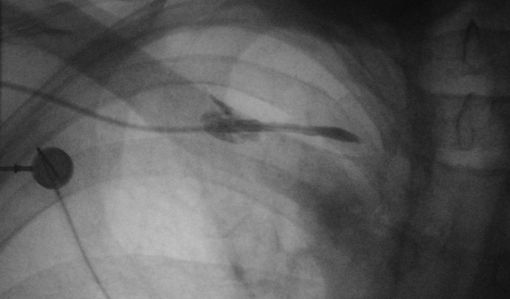

Normale Auffüllung der Portkammer und der proximalen Anteile des Portkatheters bis zum Unterrand der rechten Klavikula.

Hier findet sich ein Austritt des Kontrastmittels in die paravasalen Gewebe mit Kontrastmittelstraße nach infraklavikulär rechts lateral und um den Katheter herum.![]() |